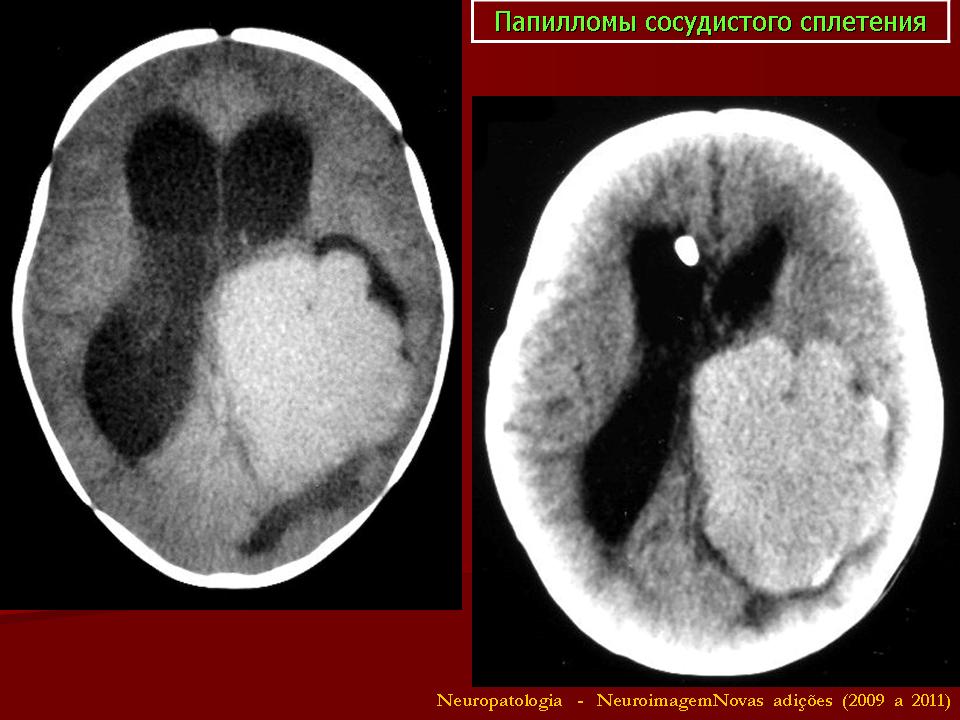

Папилломы сосудистых сплетений.

Хориоид папиллома макроскопически имеет вид «цветной капусты», т. е. узла с мелкогранулярной дольчатой поверхностью, темно-красного цвета, плотной консистенции с преимущественной локализацией в просвете желудочков. Опухоль хорошо отграничена от стенок желудочка и имеет тесную связь с сосудистым сплетением. Исключение составляет хориоидкарцинома, которая прорастает мозговое вещество на большом протяжении. Значительная часть этих новообразований локализуется пара- и перивентрикулярно. Под микроскопом типичная хориоидпапиллома имеет строение, аналогичное структуре ворсин сосудистого сплетения. Она представлена скоплениями сосочков различного размера и формы. Сосочки обладают стромой в виде сосудистого стержня и выстланы слоем многорядного хориоидного эпителия.